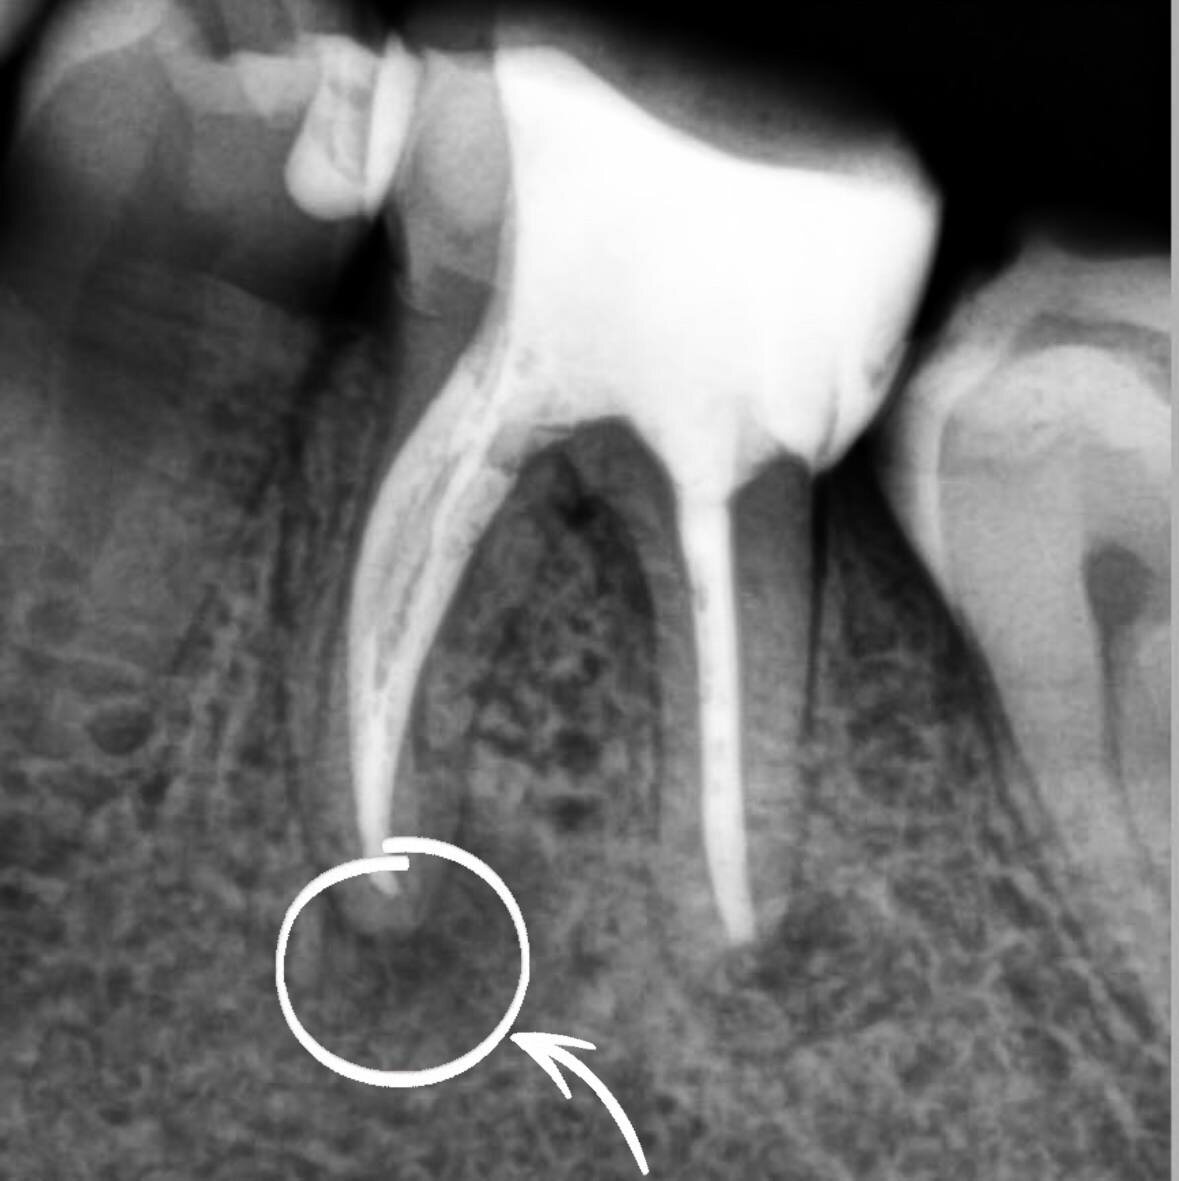

Пациент, обратился с жалобами на кровоточивость десен, неприятный запах изо рта. При осмотре был выявлен зуб, с негерметичной пломбой, провоцирующей застревание пищи и последующую кровоточивость десны. На рентгенологическом исследовании выявлен участок деструкции костной ткани. При снятии пломбы был неприятный запах из корневых каналов, что вызывало неприятный запах изо рта.

Проведено лечение зуба с использованием операционного микроскопа, лечение проходило в несколько этапов.